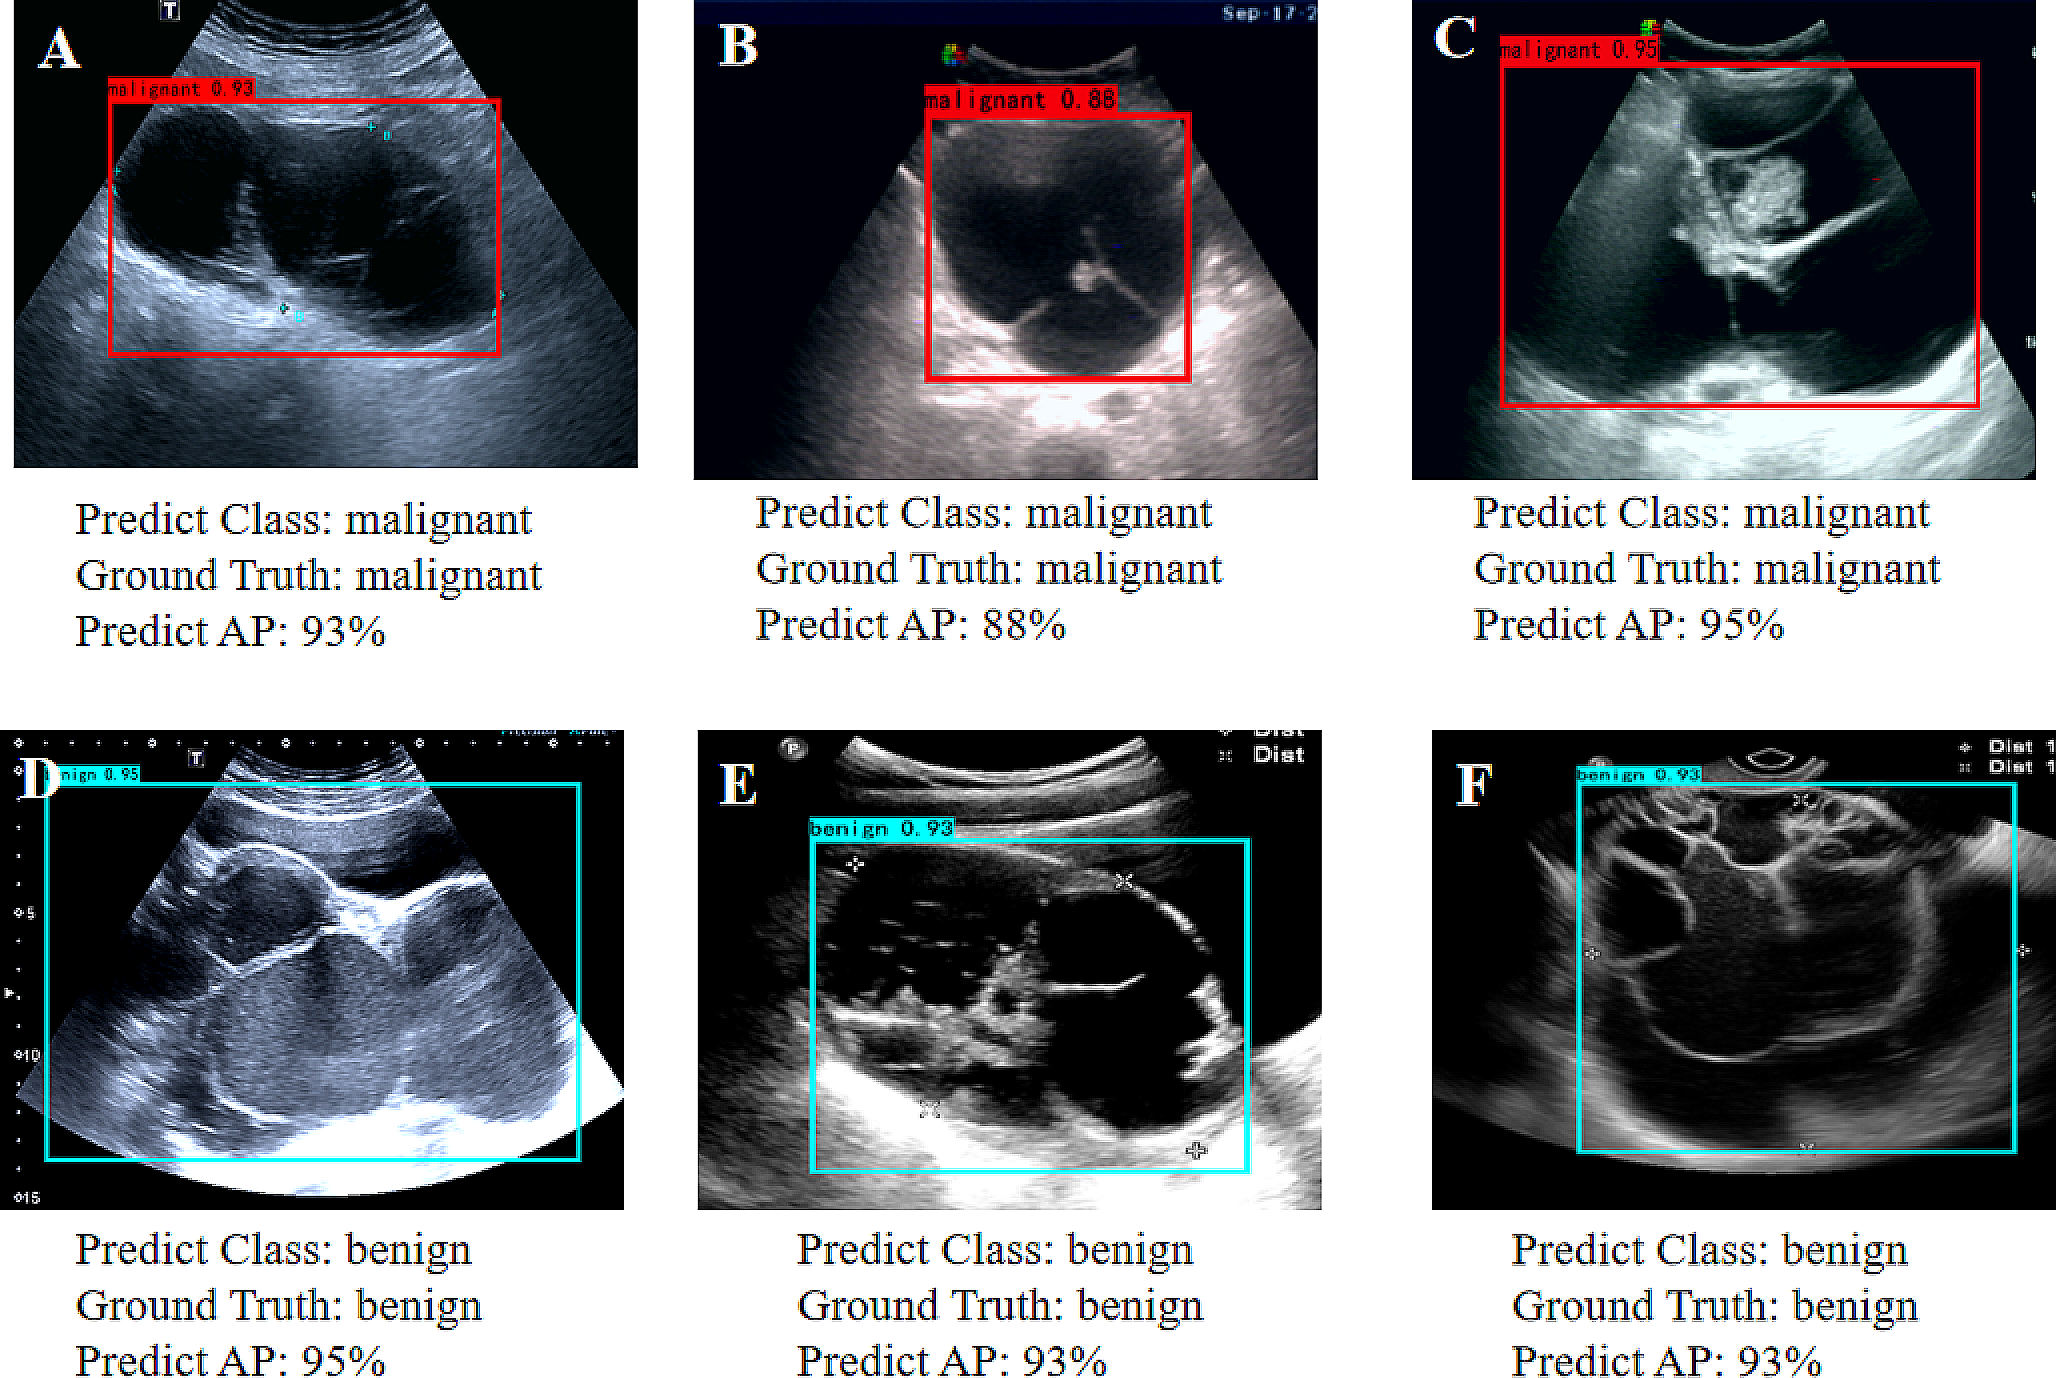

The performance of the detection DL model is shown in Fig. 3. The average precision of the precision-recall curve was 98.68% (95% CI: 0.95–0.99) for benign masses (Fig. 3A) and 96.23% (95% CI: 0.92–0.98) for malignant masses (Fig. 3B). When applied to US imaging of adnexal masses, the model showed the potential to identify nodules in benign and malignant categories (Fig. 4).

Fig. 4

Images with O-RADS US category 4 masses detected using the model. (A) High-grade serous carcinoma in a 70-year-old female patient, (B) Borderline serous tumor in a 57-year-old female patient, (C) Brenner (borderline) in a 69-year-old female patient, (D) Endometriosis cyst in a 22-year-old female patient, (E) Teratoma in a 22-year-old female patient, (F) Mucinous cystadenoma in a 47-year-old female patient. The red and blue bounding box within each imaging indicates the adnex masses delineated by the detection model